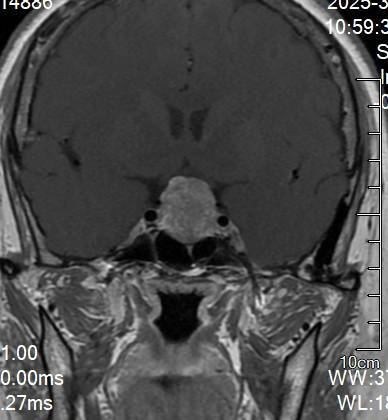

以案解析丨垂體腺瘤合并腦膜瘤處置策略

一位67歲的患者,7年前在體檢中通過MR和CT掃描發(fā)現(xiàn)垂體腺瘤合并額部小腦膜瘤。垂體腺瘤位于鞍內(nèi),無侵襲;額部腦膜瘤表現(xiàn)為明顯骨化。由于當時患者無明確臨床癥狀,因此選擇觀察隨診。近期復(fù)查結(jié)果:患者近期復(fù)查的MR和CT掃描顯示,垂體腺瘤仍位于鞍內(nèi),但比較之前略有增大,不過左側(cè)出現(xiàn)輕微侵襲海綿竇的跡象;額部腦膜瘤大小無明顯變化,骨化情況與前一致,見下【圖1-3】。患者自己感覺身體狀況良好,無明顯不適。處置方案探討:1、繼續(xù)觀察:(1)腦膜瘤:鑒于腦膜瘤在過去7年中未見明顯變化,且表現(xiàn)為骨化病變,無壓迫癥狀,可繼續(xù)觀察隨診。(2)垂體腺瘤:對于垂體腺瘤,盡管出現(xiàn)左側(cè)微侵襲海綿竇的跡象,但患者目前無癥狀,也可選擇定期隨診觀察,密切監(jiān)測病情進展。2、手術(shù)切除(垂體腺瘤):唯一的手術(shù)指征是垂體腺瘤出現(xiàn)侵襲性生長,特別是侵襲海綿竇的情況。如果腫瘤繼續(xù)增大且引起臨床癥狀(如視力下降或激素分泌異常),可考慮手術(shù)干預(yù)。最終決定:經(jīng)過與患者及家屬的充分溝通,考慮到患者的年齡已接近70歲,且目前自覺無任何不適,最終決定繼續(xù)觀察隨診,定期復(fù)查影像和相關(guān)指標。

宗緒毅醫(yī)生的科普號2024年12月05日84